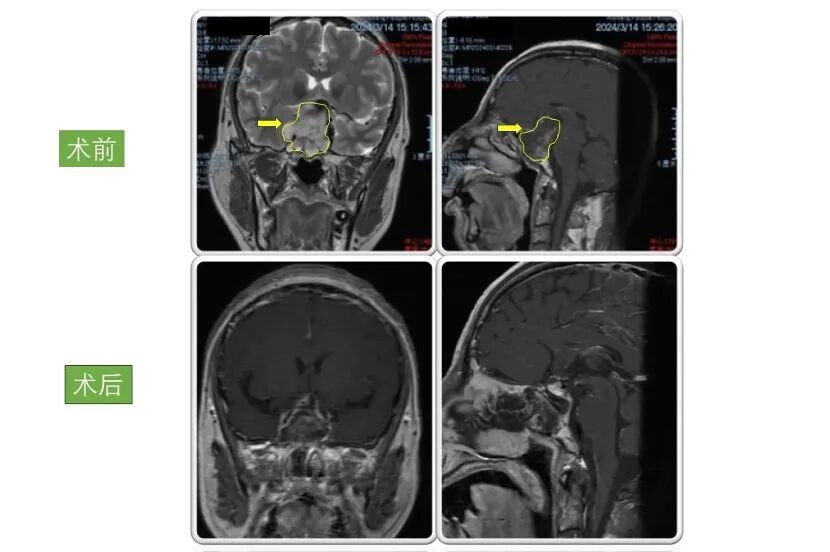

患者3:

男性,50岁,因“头晕伴四肢乏力及小便失禁2周”入院。入院检查显示巨大垂体腺瘤,大小为6.5×3×3cm。

术后患者症状好转,小便失禁症状消失,病情稳定后出院,现恢复良好,定期复查。